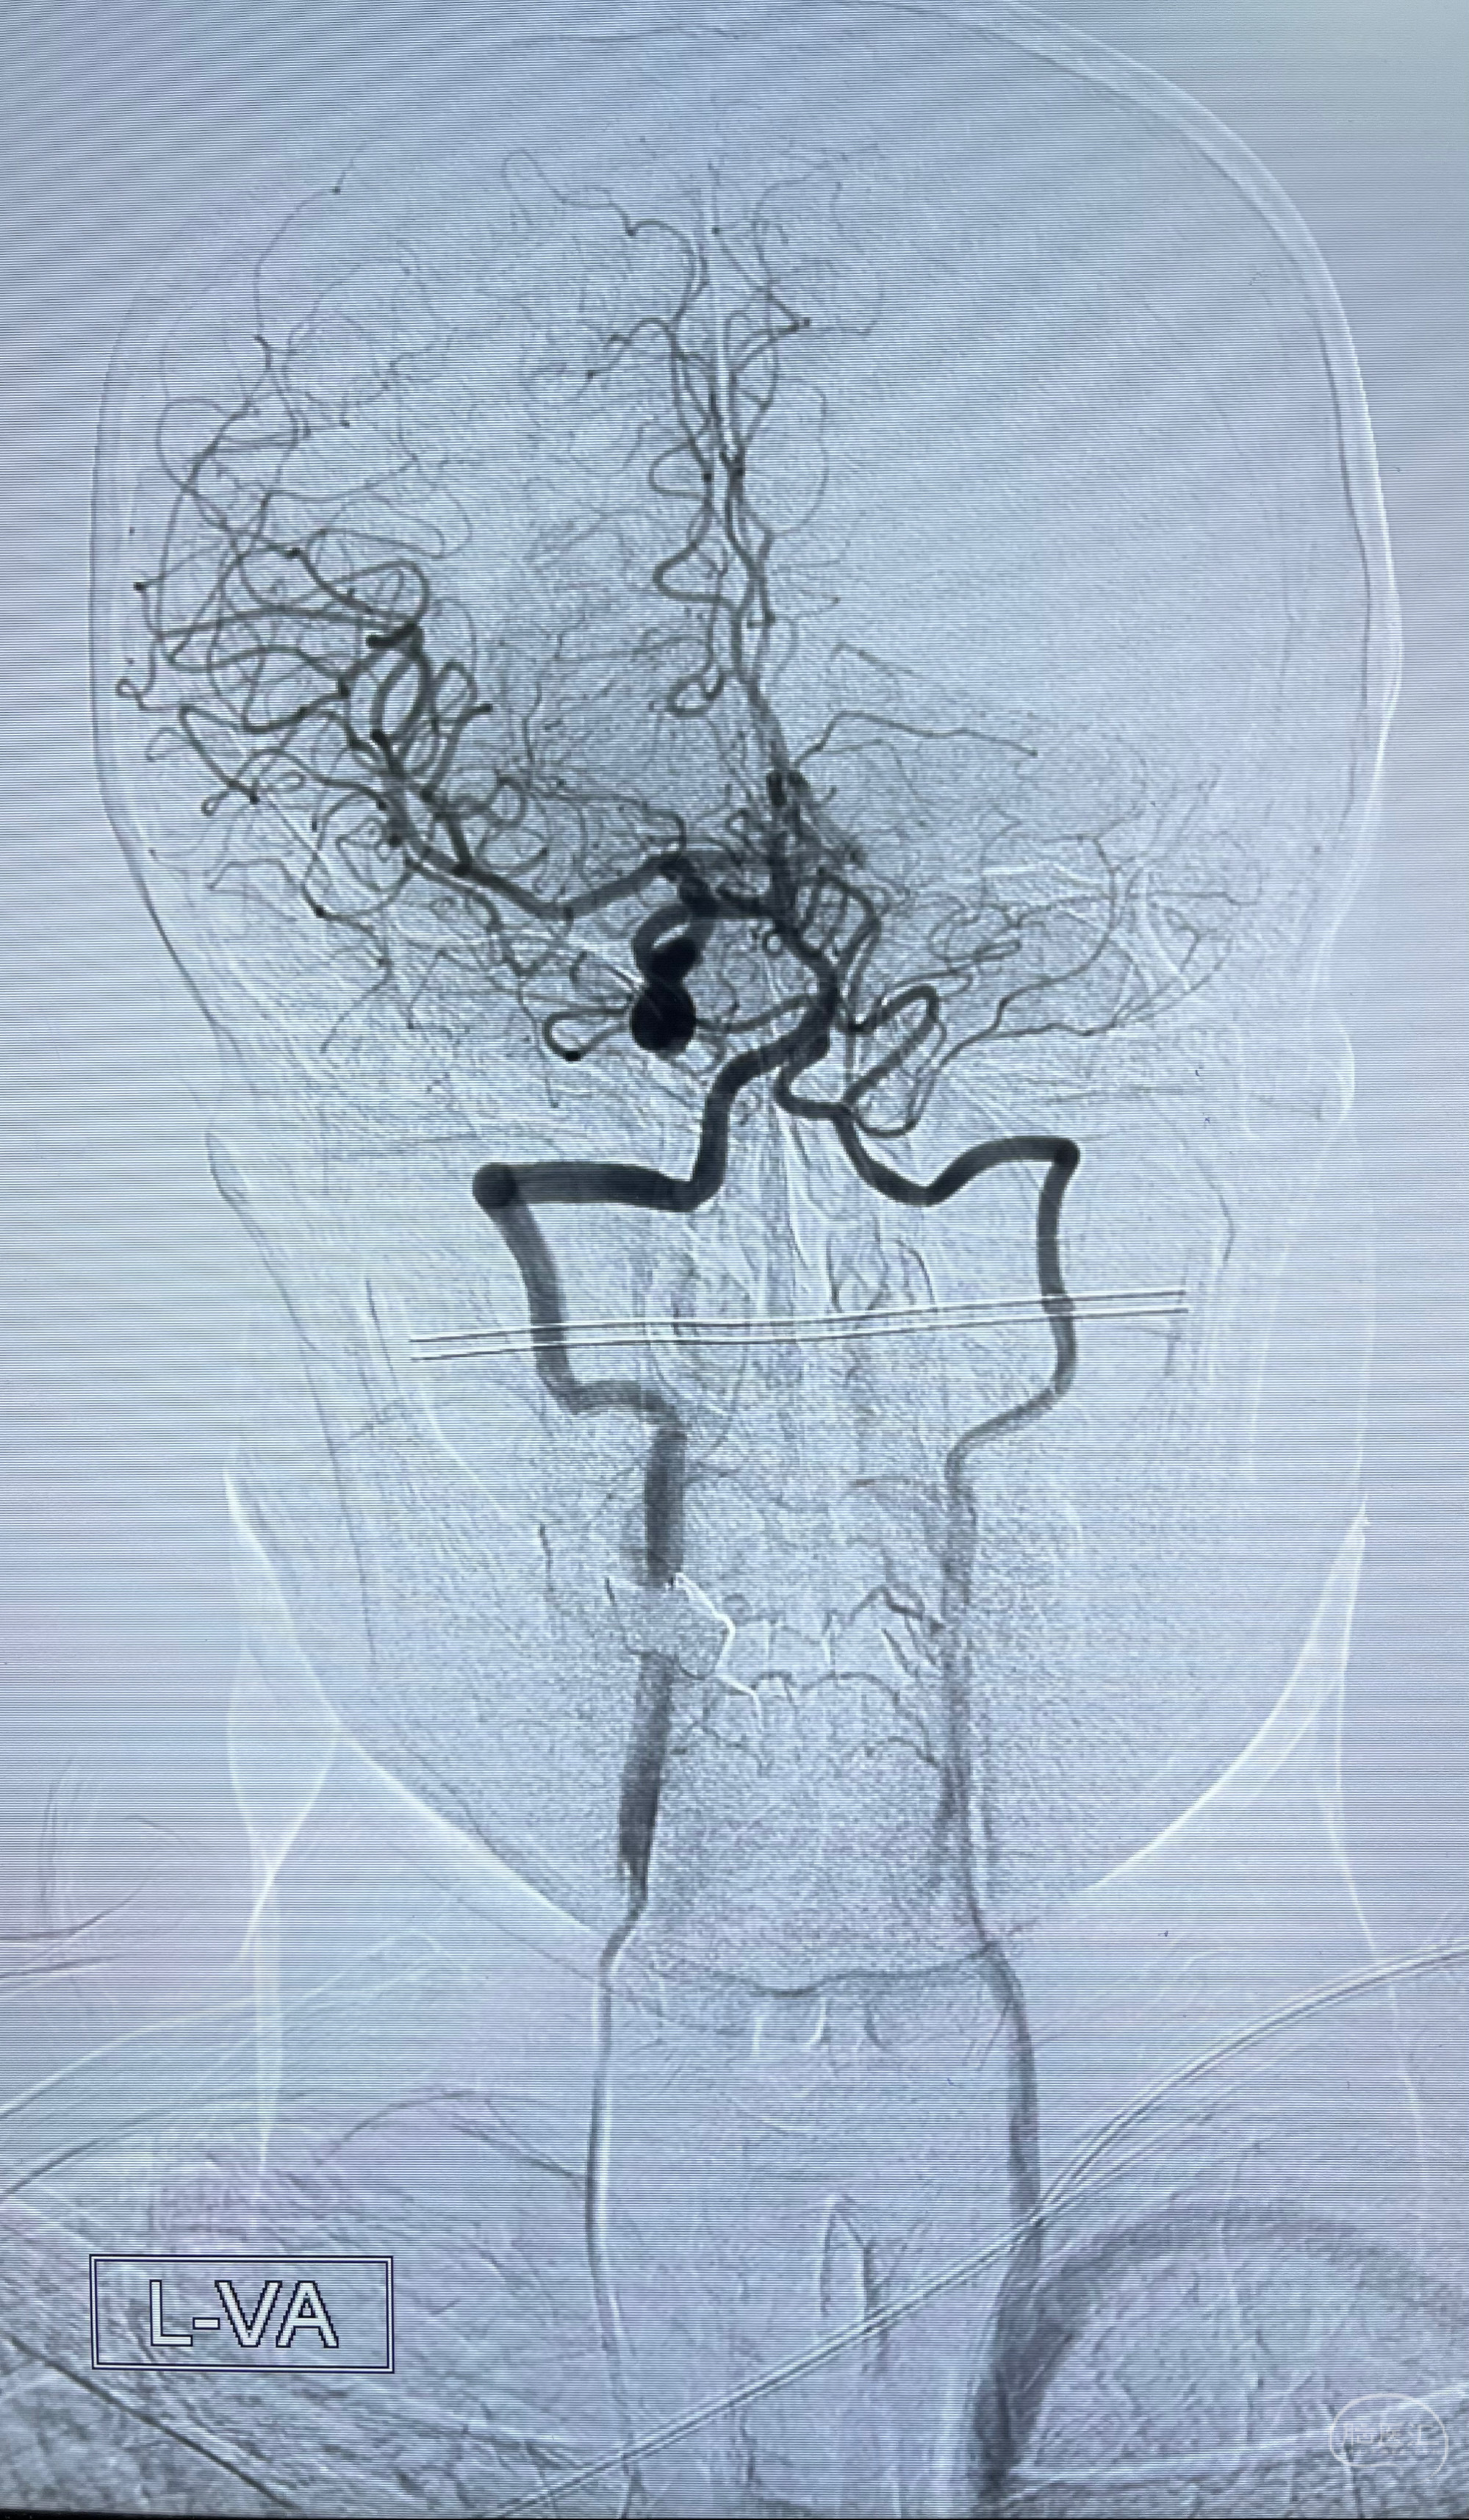

脑血管造影2023.03.06:右侧颈内动脉颈段至岩骨段闭塞,可见后后循环通过原始三叉动脉吻合代偿至海绵窦段,后交通区可见囊状造影剂填充影,左侧锁骨下动脉呈“残端”改变,呈“右侧颈总动脉支架成形术后改变”,支架内血流通畅,可见后交通吻合显影至左侧大脑后动脉,并可见左枕动脉吻合椎动脉至锁骨下动脉

1.右侧颈内动脉及左侧锁骨下动脉闭塞

2.右侧颈内动脉由后循环经右侧后交通动脉前向代偿显示

3.右侧颈内动脉眼动脉段近后交通动脉处重度狭窄伴前壁不规则动脉瘤

2.狭窄远端颈内动脉由左侧颈内动脉经左侧后交通动脉—基底动脉顶—右侧后交通—右侧颈内动脉—右侧大脑中动脉途径代偿

左侧颈内动脉经左侧后交通动脉—基底动脉顶—右侧后交通—右侧颈内动脉—右侧大脑中动脉途径代偿